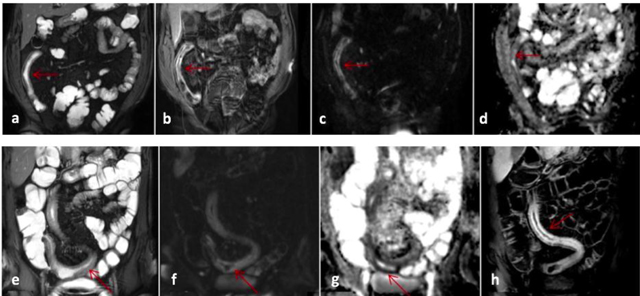

Figure 2

MR images of a patient with Crohn’s disease involving distal ileum (a–e) and another patient with involvement of a long segment of distal ileum and ileocecal junction (e–h). The images of the first patient show wall thickening and mural T2 hyperintensity on coronal FIESTA image (a), contrast enhancement along thickened ileal wall (b), mural diffusion restriction as suggested by DWI hyperintensity (c) with corresponding signal decrease along thickened ileal wall on ADC mapping (d). The images of the second patient show diffuse mural T2 signal increase with ileal wall thickening on coronal FIESTA image (e), mural DWI hyperintensity along involved ileal segment (f) with corresponding mural hypointensity on ADC mapping consistent with restricted diffusion (g) and mural contrast enhancement after intravenous gadolinium (h).